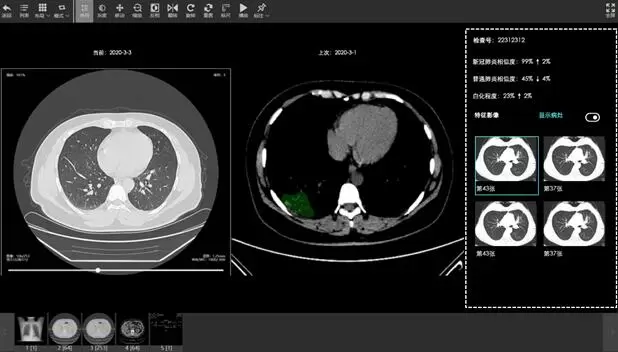

火神山医院是湖北首个“小汤山模式”医院,收治的全部是新冠确诊病例,患者病情存在随时恶化风险,AI在治疗中的角色不只是入院诊断,还包括全流程的监测、对比、观察和不同阶段的精细化诊断。基于丰富的CT影像样本,达摩院训练了全新的AI模型,可精准识别CT影像病灶位置并算出病灶占比的变化数值,由此可捕捉患者治疗全程病情变化的蛛丝马迹,AI诊断将覆盖新冠患者入院到出院全过程,帮助医生及时调整诊疗方案,降低重症转化率。

火神山医院目前仍有近千名患者。据官方数据,湖北出院患者平均住院20天,每3-4天需进行一次CT影像诊断,每位患者住院全程平均约有2000张以上CT影像,医生如果每次都依靠人工阅片并比对患者过往影像资料需要耗费极大精力。医疗AI解决了这一难题。公开资料显示,达摩院CT影像AI可在20秒内完成一次诊断(计算时间最短仅2秒),且准确率高达96%以上,大大节省医疗资源。

达摩院医疗AI的CT影像分析,可显示病灶位置和占比变化数值

据悉,此次在“火神山”上线的CT影像AI技术由达摩院医疗AI团队与古珀科技联合研发。